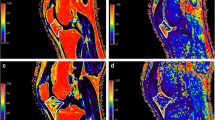

In knee OA patients, the T2FS-hyperintense IPFP regions demonstrated significantly higher values of Ktrans (see Fig. 2) and Ve compared to tissue with normal signal intensity (0.039 min−1 vs. 0.025 min−1 for Ktrans and 0.157 vs. 0.119 for Ve). Kep and Vp were higher within T2FS-hyperintense lesions compared to tissue with normal signal intensity (median Kep 197.57 vs. 163.49 and median Vp 2.09 vs. 1.03, respectively). However, these differences were not statistically significant for both Kep (p = 0.079) and Vp (p = 0.363). In both controls and PFP patients, all DCE-MRI perfusion parameters were not significantly different between IPFP tissue with and without a T2FS-hyperintensity. In PFP-patients, a Ktrans of 0.014 min−1 and Kep 0.113 min−1 in IPFP tissue with normal signal intensity and a Ktrans of 0.011 min−1 and Kep 0.173 min−1 in tissue with T2FS-hyperintensity was found. In controls, the median Ktrans was 0.014 min−1 and median Kep was 0.122 min−1 in IPFP tissue with normal signal intensity and in tissue with T2FS-hyperintensity these values were 0.010 and 0.091 min−1, respectively. Moreover, all DCE-MRI perfusion parameters were higher in both the hyperintense lesions and normal IPFP tissue in the OA group. All DCE-MRI results are shown in Table 2.